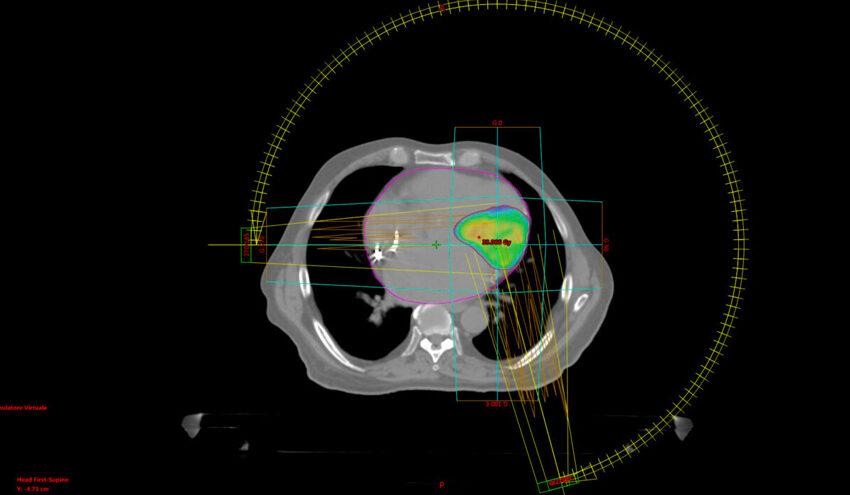

“L’intervento di radioablazione – spiega il dottor Francesco Cellini, assistente medico con incarico di alta specializzazione in radioterapia Policlinico Universitario A. Gemelli IRCCS – viene effettuato con il paziente sveglio (non si sente alcun dolore durante la procedura) e costantemente monitorato per i parametri vitali. Il fascio di radiazioni ultra-concentrate (‘collimate’) viene indirizzato contro il bersaglio individuato in precedenza dai cardiologi con la mappatura elettro-anatomica. L’intervento dura una mezz’ora circa. La parte più difficile consiste nel centrare costantemente con grande precisione il bersaglio, mentre il cuore si muove (l’intervento si effettua a cuore battente), senza danneggiare le strutture sane. Il sistema ‘spara’ il fascio di raggi fotonici solo quando è sicuro di colpire con precisione il bersaglio e la guida viene fornita da immagini TAC (acquisite prima di iniziare il trattamento per la ‘centratura’) e da un’immagine di riferimento tridimensionale, acquisita da uno scanner a infrarossi che monitorizza la superficie toracica del paziente durante tutta la durata del trattamento, per essere certi che il bersaglio non si sposti.

“La radioterapia – prosegue il dottor Cellini - è un trattamento non invasivo, che utilizza radiazioni elettromagnetiche (un’energia simile a quella che si utilizza per le radiografie e per le TAC), estremamente concentrate su un punto più o meno grande. Nell’applicazione cardiologica (al momento nel mondo sono meno di 50 i pazienti trattati con questa tecnica) possono essere utilizzate tre diverse tecnologie. Al Gemelli ne abbiamo due su te, nella loro versione più avanzata. Per la prima volta al mondo, per un intervento di radioablazione, abbiamo utilizzato l’apparecchio VARIAN Edge, una vera e proprio Ferrari della radioterapia (in tutta Europa ci sono solo 22 macchine come questa)”.

“Grazie ad una stretta collaborazione con la Fisica Sanitaria del nostro Dipartimento – prosegue il dottor Cellini - abbiamo potuto eseguire il primo trattamento documentato con un Linac dedicato specificamente alla radioterapia stereotassica (Varian- Edge) applicando, oltre alle procedure di controllo del movimento preliminari alla terapia, anche un controllo continuo durante l’intera seduta. Nel nostro centro abbiamo peraltro a disposizione anche un'altra apparecchiatura all’avanguardia per la Radioterapia: il sistema MRIdian (ViewRay). Questo sistema (a nostra disposizione tra i primi esemplari al Mondo, già dal 2017) permette di controllare costantemente la posizione del bersaglio da trattare e seguirne gli eventuali spostamenti attraverso una guida d’immagine con risonanza magnetica, associata ad un rivoluzionario approccio per la radioterapia che consente anche di riaggiornare il calcolo delle distribuzioni di dose prima di ogni seduta di trattamento”.

“La Radioterapia – ricorda il Professor Vincenzo Valentini, Ordinario di Radiologia all’Università Cattolica campus di Roma e Direttore della UOC di Radioterapia Oncologica, Dipartimento di Diagnostica per Immagini, Radioterapia Oncologica ed Ematologia Policlinico Universitario A. Gemelli IRCCS - benché più diffusamente impiegata come uno delle tre principali presidi dei trattamenti oncologici (accanto a quello sistemico e quello chirurgico), ha da sempre una quota di indicazioni cliniche non oncologiche. In particolare, proprio in ambito cardiologico sono state condotte in passato esperienze di trattamento radiante per la prevenzione del rischio di re-stenosi coronariche dopo angioplastica. Il moderno trattamento che proponiamo in questo progetto congiunto – prosegue il professor Valentini - si basa sulla radioterapia stereotassica, la più precisa e collimata tipologia di moderna radioterapia. In particolare questo trattamento viene eseguito in una singola seduta che rilascia una dose di radiazioni elettromagnetiche tanto elevate, quanto localmente concentrate, sullo specifico bersaglio oggetto del trattamento, in questo caso il cuore e, in particolare, sulla zona individuata come responsabile delle aritmie ventricolari. In gergo si parla di radiochirurgia o radioablazione”.